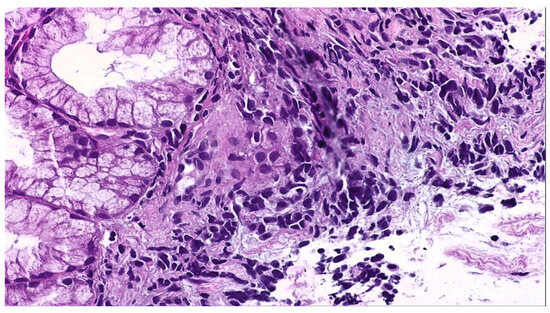

2. Detailed Case Description

2.1. Diagnostic Evaluation